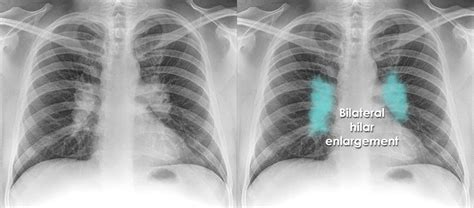

The diagnostic approach to a hilar lung mass begins with imaging. Chest X-rays can provide an initial indication of a mass, but CT scans offer more detailed information about the mass's size, location, and potential invasion into surrounding structures. PET scans can help assess the mass's metabolic activity, which is useful in distinguishing benign from malignant lesions and identifying potential metastases. Ultimately, a tissue diagnosis through biopsy is necessary to determine the mass's nature and guide treatment.